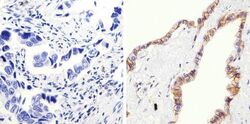

Supportive validation

- Submitted by

- Invitrogen Antibodies (provider)

- Main image

- Experimental details

- Immunohistochemistry analysis of Beta-Catenin showing staining in the membrane and cytoplasm of paraffin-embedded human lung adenocarcinoma (right) compared to a negative control without primary antibody (left). To expose target proteins, antigen retrieval was performed using 10mM sodium citrate (pH 6.0), microwaved for 8-15 min. Following antigen retrieval, tissues were blocked in 3% H2O2-methanol for 15 min at room temperature, washed with ddH2O and PBS, and then probed with a Beta-Catenin Rabbit Polyclonal Antibody (Product # 71-2700) diluted in 3% BSA-PBS at a dilution of 1:100 overnight at 4°C in a humidified chamber. Tissues were washed extensively in PBST and detection was performed using an HRP-conjugated secondary antibody followed by colorimetric detection using a DAB kit. Tissues were counterstained with hematoxylin and dehydrated with ethanol and xylene to prep for mounting.